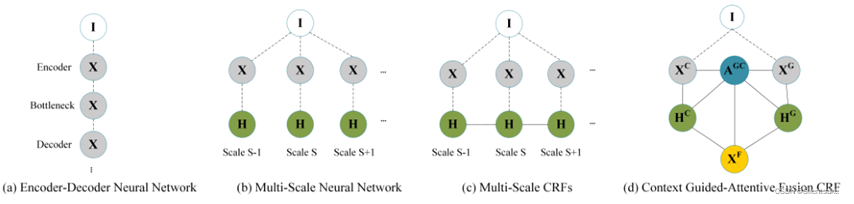

进一步提出了一个新的情境引导注意CRF模块来进行特征融合,其动机来自两个方面。提出的CGA-CRF的图模型如图3所示。使用CGA-CRF进行特征融合有两个原因。首先,通过最大化概率分配分割标签可能会由于相邻体素共享相似的特征表示而导致错误的边界分割;其次,以往的作品采用通道级联或元素求和机制,融合不同来源的特征。但是,这些机制简化了不同源特征图之间的关系,可能导致信息丢失。与以往的相关工作不同,作者利用概率图形模型的推理能力,采用条件随机场模型来学习最优的潜在融合特征。由于来自不同情境的信息可能对最终结果有不同程度的影响,作者整合了CGA-CRF的注意门,以调节特征之间的信息流动。作者还进一步展示了使用顺序卷积操作的CGA-CRF均值场更新的实现,这使得CGA-CRF融合模块可以作为顺序层与任何神经网络集成,并以端到端方式进行训练。与以往的编码器-解码器神经网络(图3 (a))和多尺度神经网络(图3 (b))相比,提出的CGA-CRF(图3 (d))具有较强的推理能力,可以共同学习神经网络主干编码的特征隐藏表示。提高了分割模型的泛化能力。与之前的架构如多尺度CRF(图3 ©)相比,提出的CGA-CRF模型首先通过直接建模网络中的成本能量使用注意门(Eq.(7))。因此,注意门通过最小化总能量成本,调节从主干神经网络编码的特征到潜在表示的信息流。

图3:先前特征融合方案的图形模型说明:(a)基本编码器-解码器神经网络,(b)多尺度神经网络,(c)多尺度CRF,以及(d)提出的上下文引导注意CRF。I表示输入的3D MRI图像。S表示特定的要素比例。XC和XGRE分别表示卷积运算和图卷积实践产生的隐藏特征。AGC表示从相应的功能XC和XG生成的注意图。最好是彩色的。